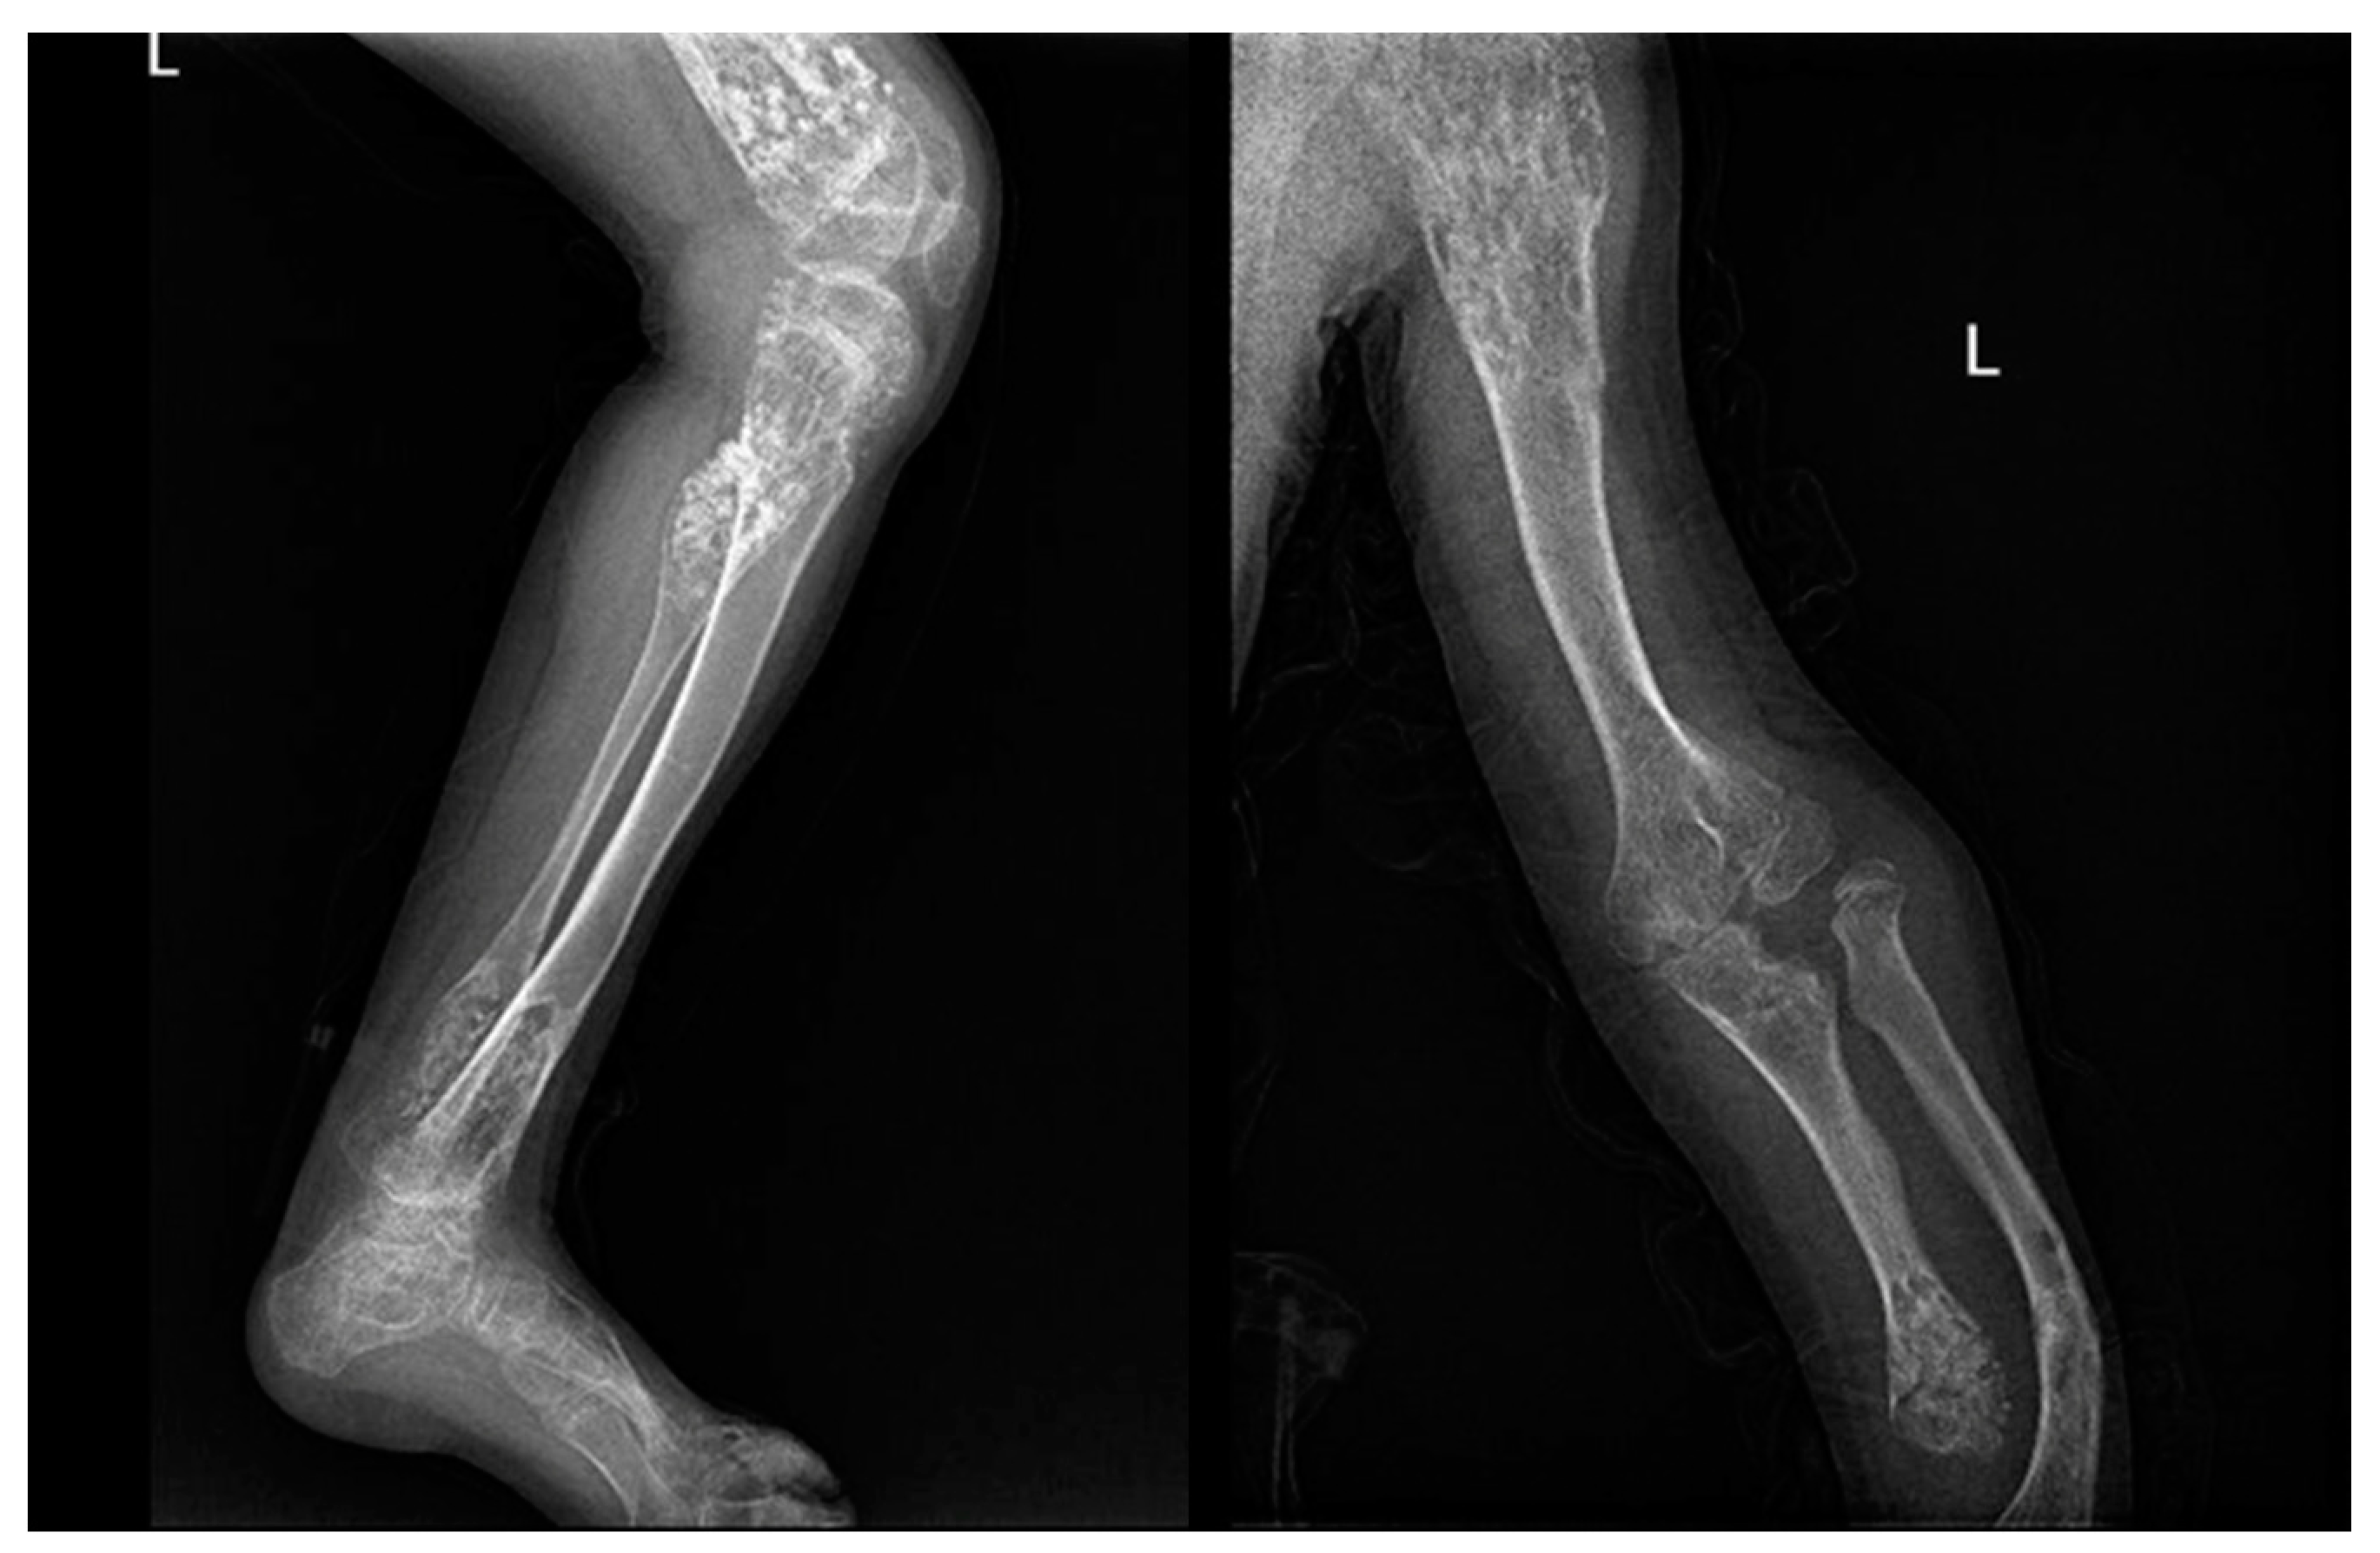

In X-ray examination, a bone-forming tumor appears as a nidus surrounded by sclerotic tissue. It may be hard to identify when it is intra-articular, therefore requiring further look examination. The second-level exam is a CT scan, which displays a small, defined nidus surrounded by a sclerotic reaction which may contain calcifications. Bone scintigraphy usually shows arterial phase uptake in the nidus due to its high vascular concentration and lower concentration in the reactive surrounding bone. There is a typical sign called the double-density sign which is diagnostic. It is fundamental to pay attention to growth plates since they can obscure the signal if the osteoid osteoma is in their proximity; therefore, it can be helpful to evaluate the contralateral side. Other imaging techniques may help the diagnostic workup, but those must be considered case by case [19,20,21] (Figure 1).

Figure 1.

X-rays and CT scan of a tibial fracture that occurred in the development site of an Osteoid osteoma.